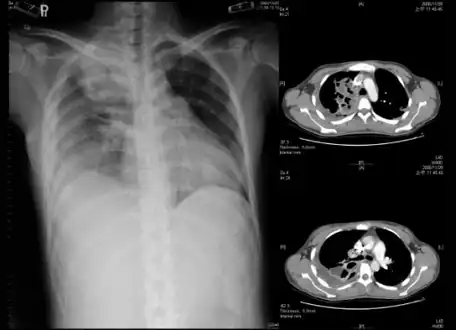

Empyema -

Empyema with abscess